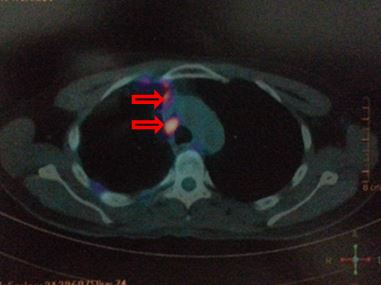

Hình ảnh PET/CT sau 8 chu kỳ Cisplatin-Pemetrexed - Bevacizumab

Nhiều nốt mờ rải rác phổi phải, màng phổi, max SUV = 4,7. Hạch cạnh khí quản 1,5 cm, max SUV = 6,4 (đầu mũi tên)